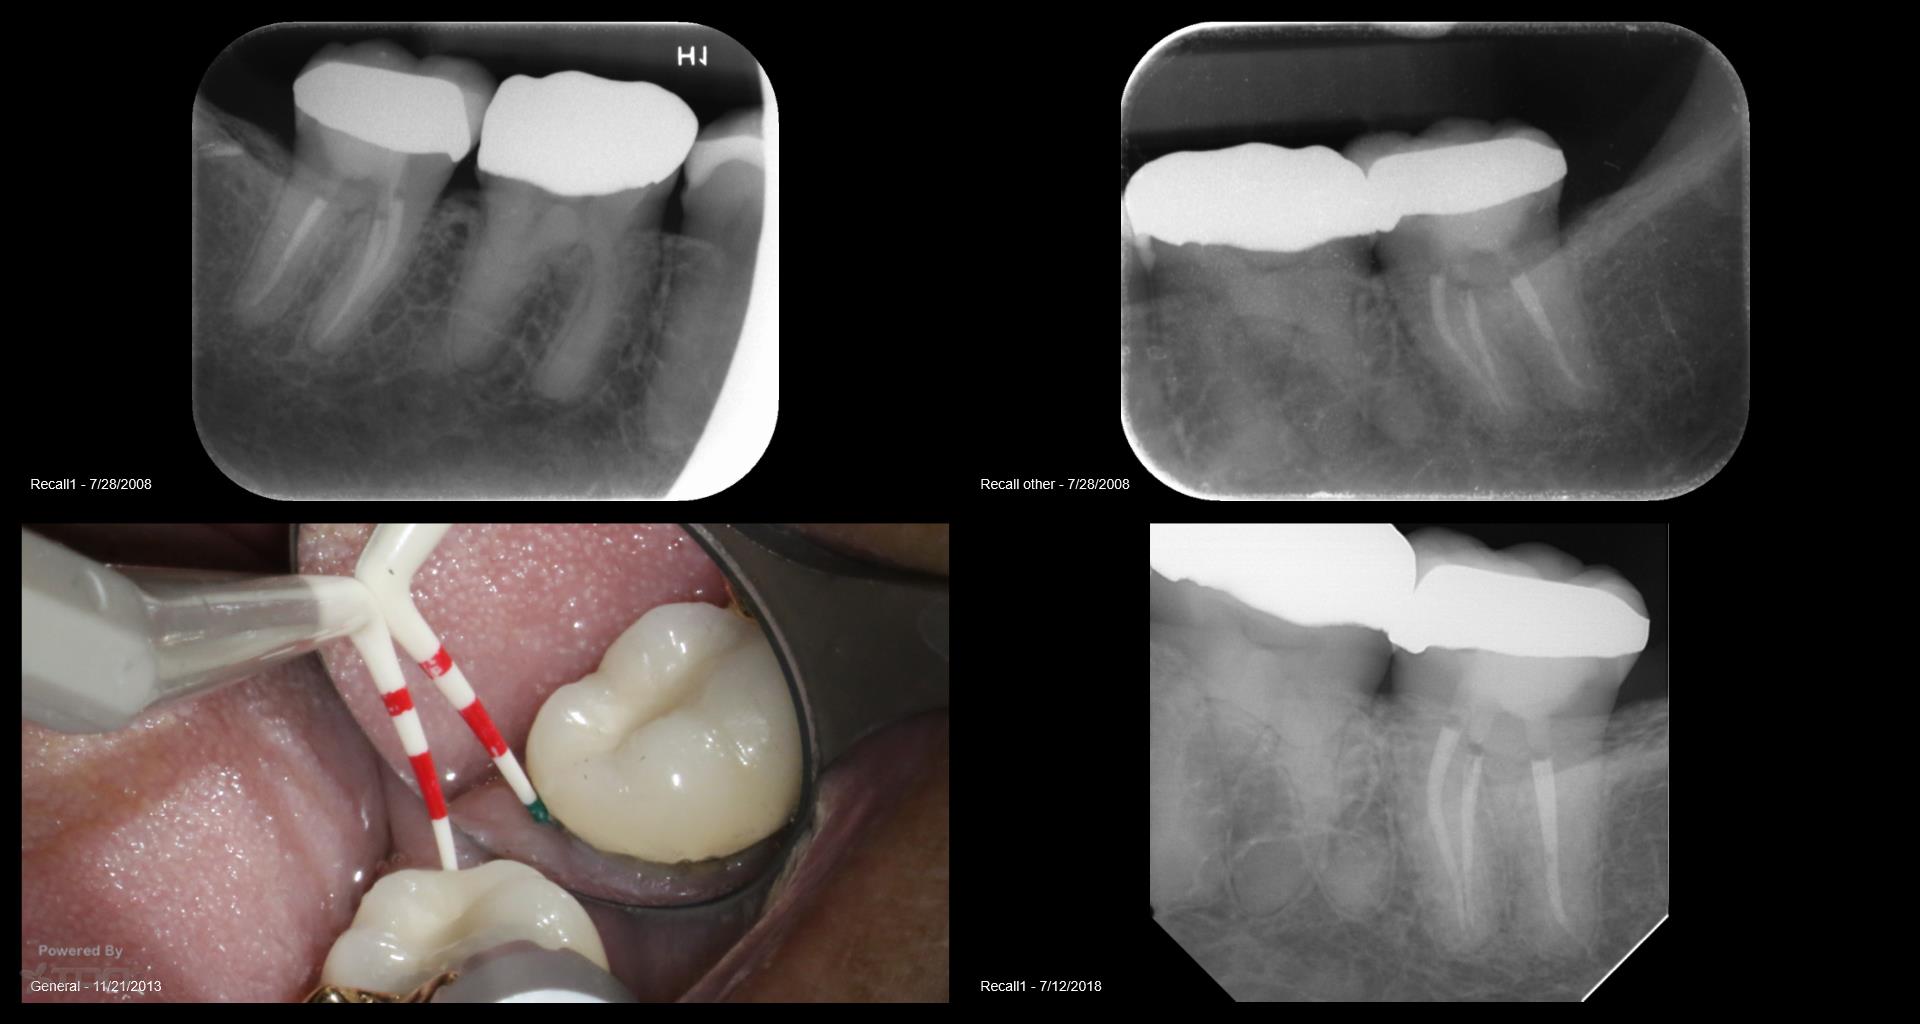

16 yr recall os a fracture

Collage-2140634747-Page00